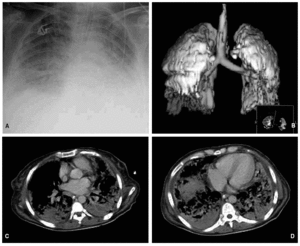

La exploración radiológica corresponde a una paciente de 43 años de edad, ingresada por una neumonía bilateral con cultivo de broncoaspirado positivo para Streptococcus agalactiae. Desarrolló un síndrome de distrés respiratorio agudo (SDRA), por lo que fue tratada mediante estrategias ventilatorias protectoras del pulmón, utilizando valores de presión positiva telespiratoria (PEEP) y volumen circulante de acuerdo con los datos aportados por la curva de presión/volumen. A los 20 días de evolución de dicho SDRA se realizó una tomografía computarizada (TC), en ventilación controlada por volumen, con un volumen circulante de 400 ml, una presión pausa de 30 cmH2O y una PEEP de 10 cmH2O. La imagen superior izquierda (A) corresponde a la radiografía de tórax simple y en la imagen superior derecha (B) se muestra la reconstrucción tridimensional de pulmón, traquea y bronquios principales, obtenida a partir de los cortes de TC torácica. Las imágenes inferiores (C y D) corresponden a cortes convencionales de la TC torácica superior y basal. Son evidentes las irregularidades de la superficie pulmonar en relación con fenómenos de fibrosis, así como la falta de aireación de los lóbulos inferiores en relación con los superiores.